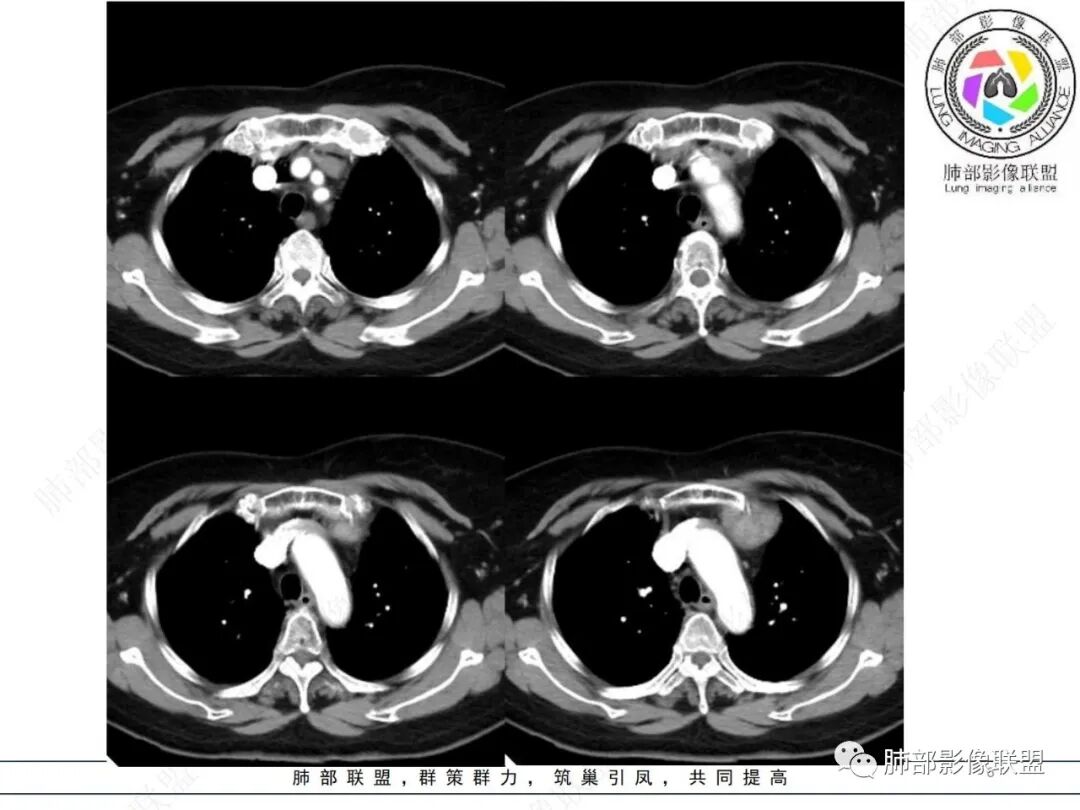

—平扫密度不高,加之缺乏与颈部甲状腺解剖关联性,胸腔内甲状腺肿可能性较小。

—强化程度及强化方式不支持常见的血管瘤及巨淋巴结增生症(CD)。

—患者血压高,应当排除副节瘤可能。病灶未见坏死区,且发生于纵隔的嗜铬性副节瘤罕见。